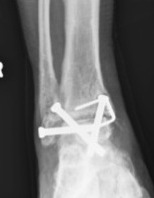

Fixation

- position foot, check with image intensifier

- +/- bone graft

- two cannulated screws from medial tibia to talus dome / neck

- +/- screw medial malleolus to talus

- +/- screw fixation fibular / onlay graft